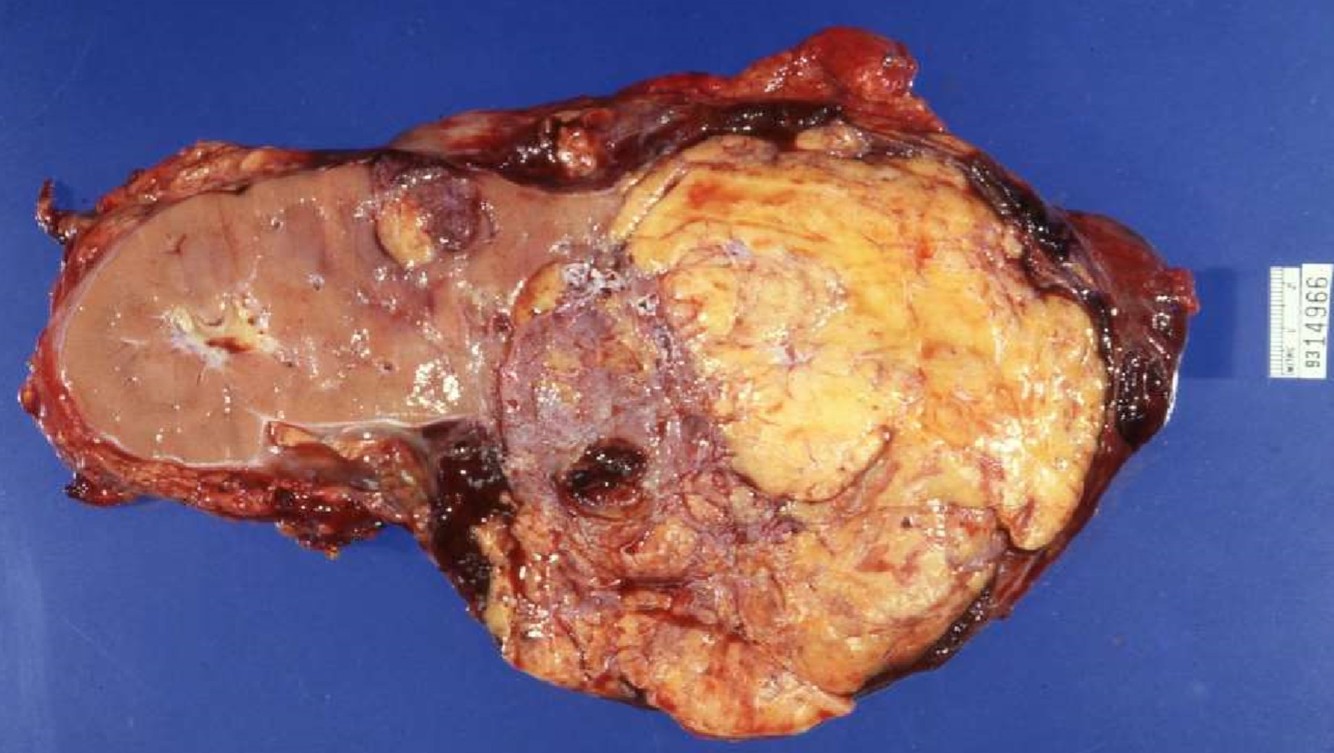

ANGIOMYOLIPOMA

- Sporadic or tuberous sclerosis

- tuberous sclerosis

- multifoca/bilateral, often associated with renal cysts/RCC

- Variants: regional nodal involvement, extrarenal disease (liver, spleen, lung), epithelioid AML

- Immunoreactive for actins and melanocytic markers

- Perivascular epitheliod cells - PEComa